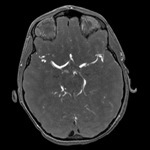

Vessels (MRA)

Axial